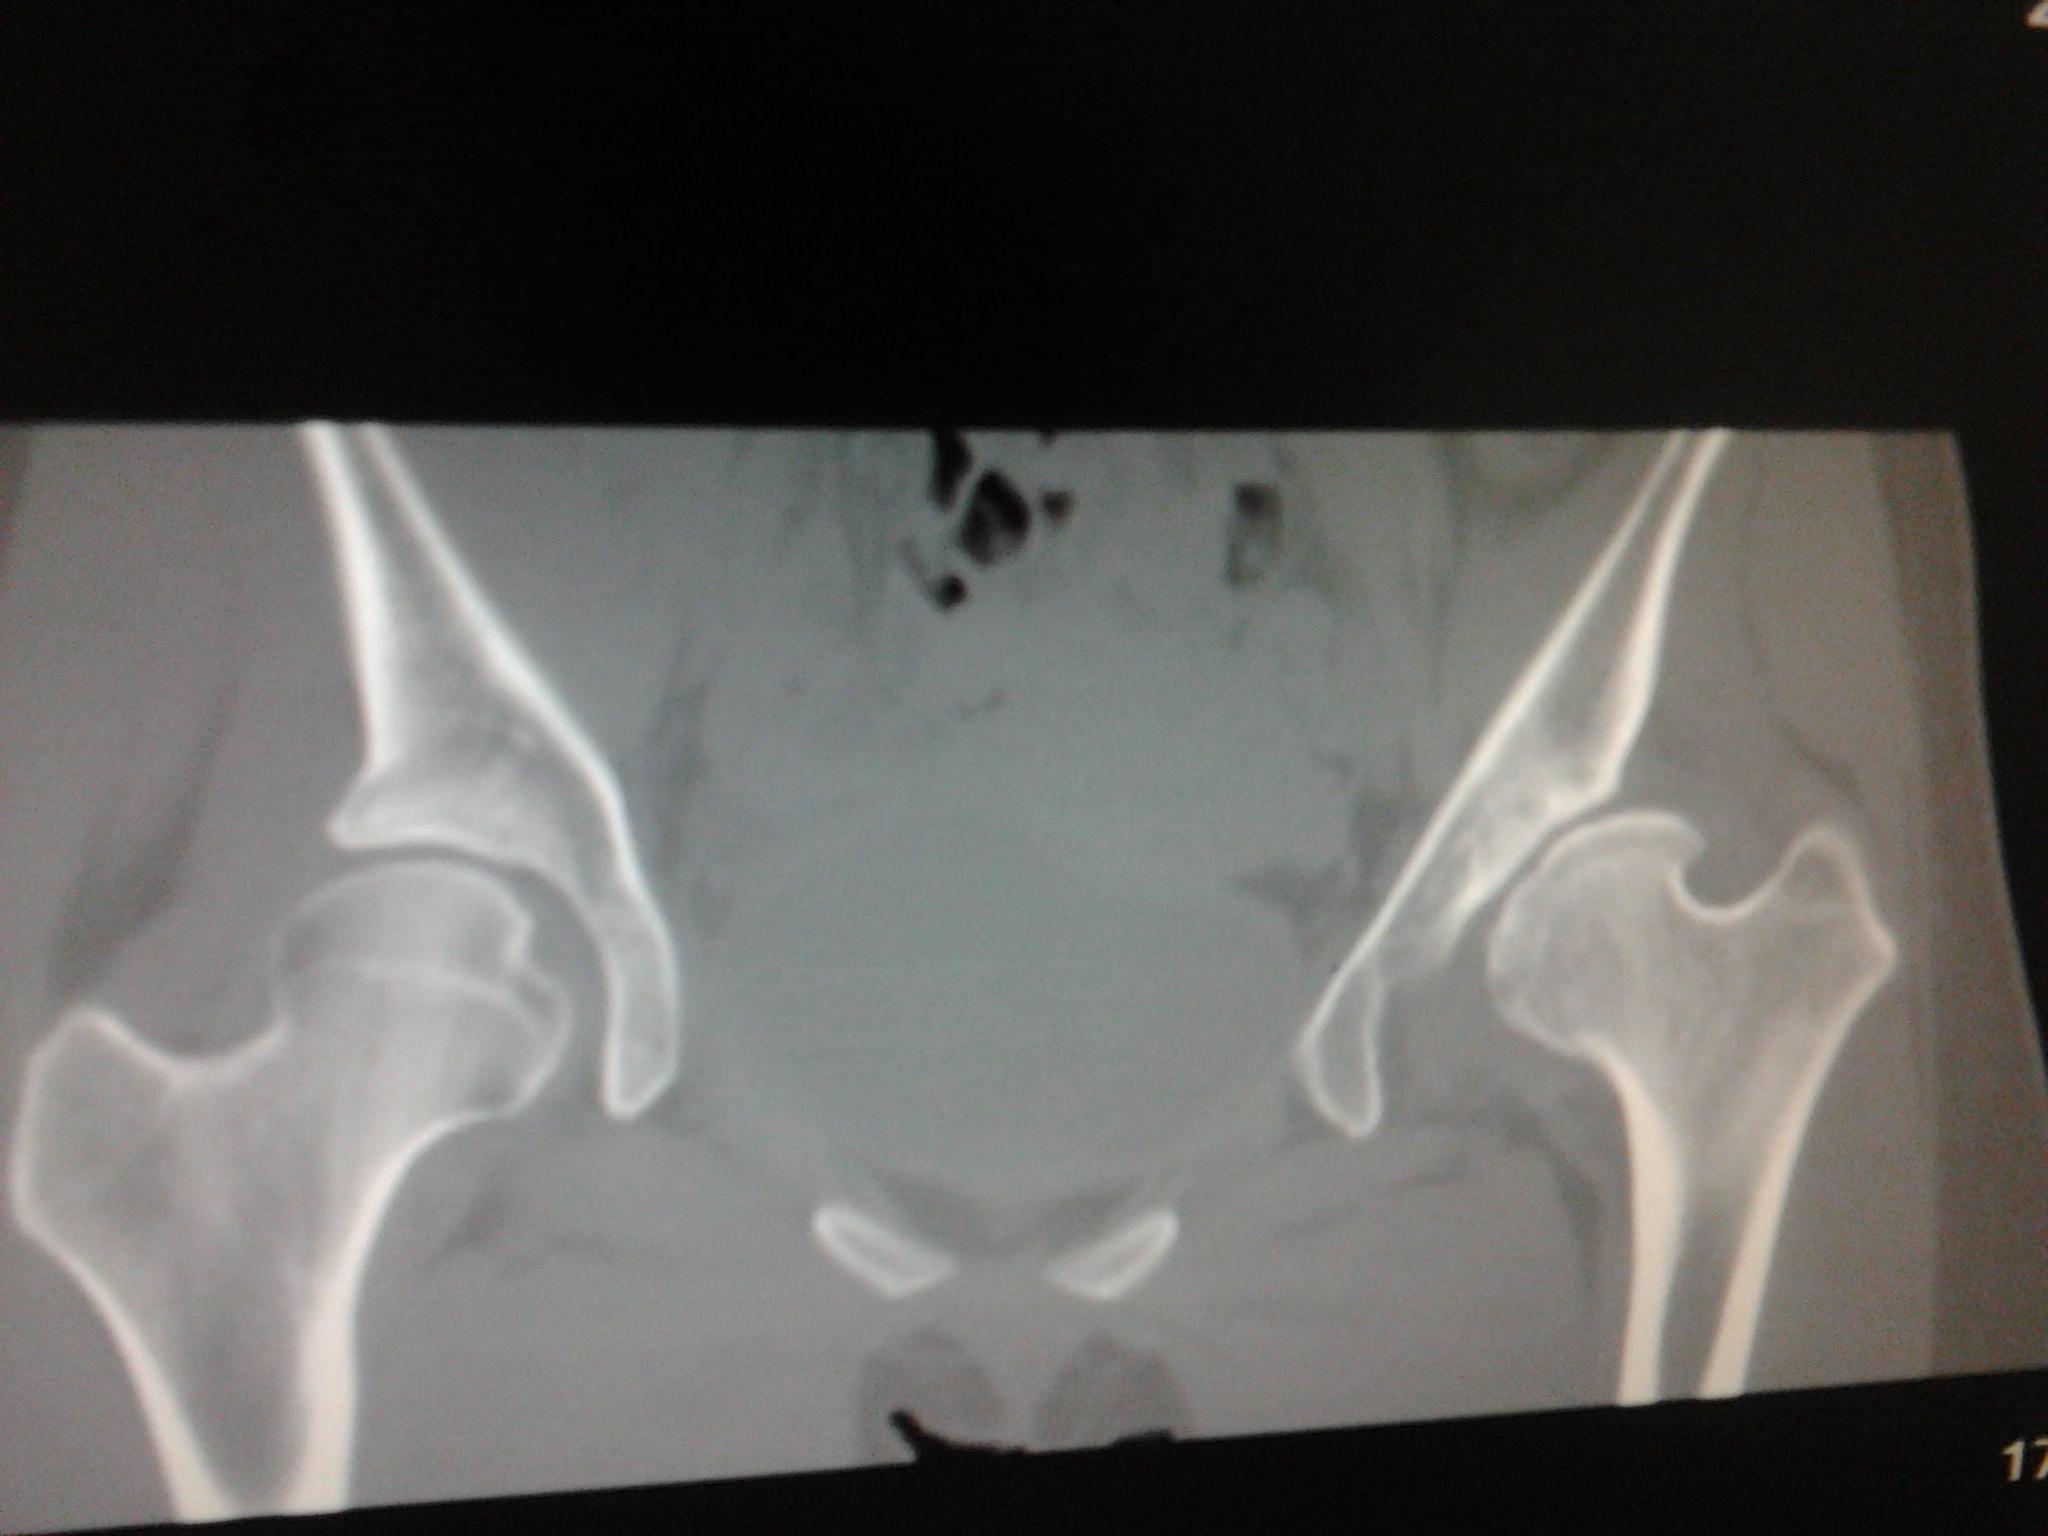

髋臼骨折,二次取内固定术后髋关节半脱位